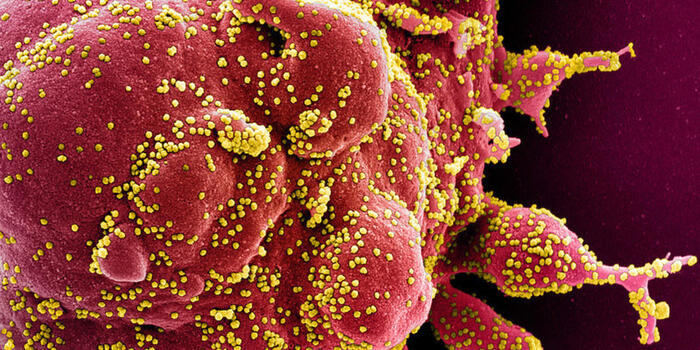

Social 13 İyul 16:09Is It Safe to Take Medication Without Consulting a Doctor?

Health 7 İyul 15:28The use of plasmapheresis in allergic diseases

Health 7 İyul 13:50Death Toll from Venezuela earthquake exceeds 3,500